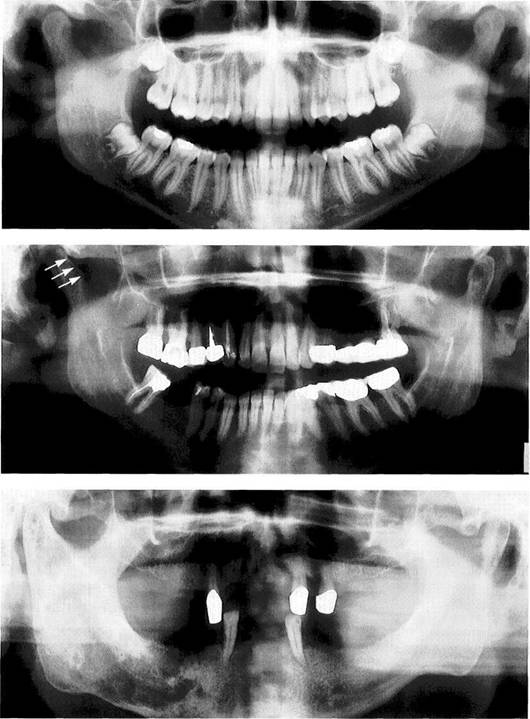

Juvenile chronic arthritis

Panoramic radiograph of a 10-year-old with chronic juvenile arthritis. Approximately 10% of children with this disease and near normal forma­tion of the facial bones exhibit de­generative changes in the condyles (Pearson and Ronning 1996). In pa­tients with severe skeletal changes ("bird-face retrognathism") the condyles always show advanced re­sorption. Early functional treat­ment can improve the skeletal problems (Pedersen et al. 1995, Paulsen 1997).

Goldenhar syndrome

Panoramic radiograph of a 6-year-old with Goldenhar syndrome (oculoauriculovertebral dysplasia). While the right ascending ramus and condyle have developed nor­mally, on the left side there is un­derdevelopment and shortening of the condylar process. In patients with syndromes, the extent of involvement of the temporo­mandibular joint is of special inter­est because this determines the type of treatment (functional jaw orthopedics, Herbst hinge appli­ance, distraction osteogenesis, re­constructive dentistry).

Pyknodysostosis

A 56-year-old man with a sponta­neous fracture of the mandible associated with pyknodysostosis. Pyknodysostosis is a rare form of sclerosing osseous dysplasia with an autosomal recessive inheritance (Maroteaux and Lamy 1962, Kark-abi 1993)..The temporomandibular joints themselves are usually not affected (Yamada et al. 1973, Zachariades and Koundouris 1984), but the osteomyelitis that fre­quently accompanies it can some­times mimic a temporomandibular joint problem (Iwu 1991, Schmitzet al. 1996).